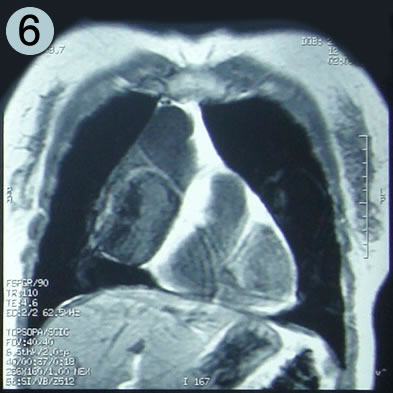

Corte Coronal en secuencia T1

Un corte coronal mas anterior al precedente: la lesión en su mayor diámetro

en relación adosada con la aurícula derecha y el cono aortico